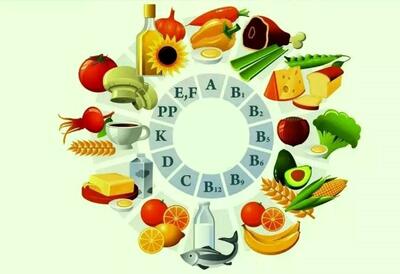

جگر مرغ یکی از اعضای داخلی بدن مرغ است که سرشار از مواد مغذی مانند آهن، ویتامین A، ویتامین B12، فولات و پروتئین است. اما یکی از نگرانیهای رایج در مورد مصرف جگر مرغ، احتمال تجمع هورمونها و سموم در آن است.

مواد غذایی حاوی B12 کدامند؟

بهترین مواد غذایی برای تامین ویتامین B12 کدامند؟

ویتامین B12، یک ویتامین ضروری برای بدن، به ویژه برای سلامت مغز و سیستم عصبی، بسیار مهم است. بسیاری از افراد برای تامین این ویتامین

گوشت قرمز منبعی غنی از آهن، پروتئین و ویتامین B12 است که با مصرف متعادل، میتواند به تقویت سیستم ایمنی و سلامت بدن در فصل زمستان کمک کند.

ویتامین ب12 به طور طبیعی در محصولات حیوانی یافت می شود و برای درمان آکنه صورت و جوش از آن استفاده بسیاری می شود.